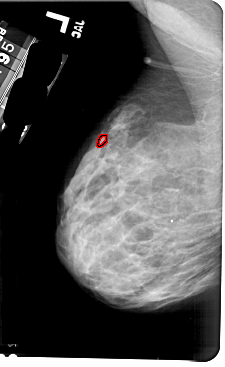

A_1797_1.RIGHT_MLO

RIGHT_MLO LINES 5491 PIXELS_PER_LINE 3046 BITS_PER_PIXEL 12 RESOLUTION 43.5 NON_OVERLAY